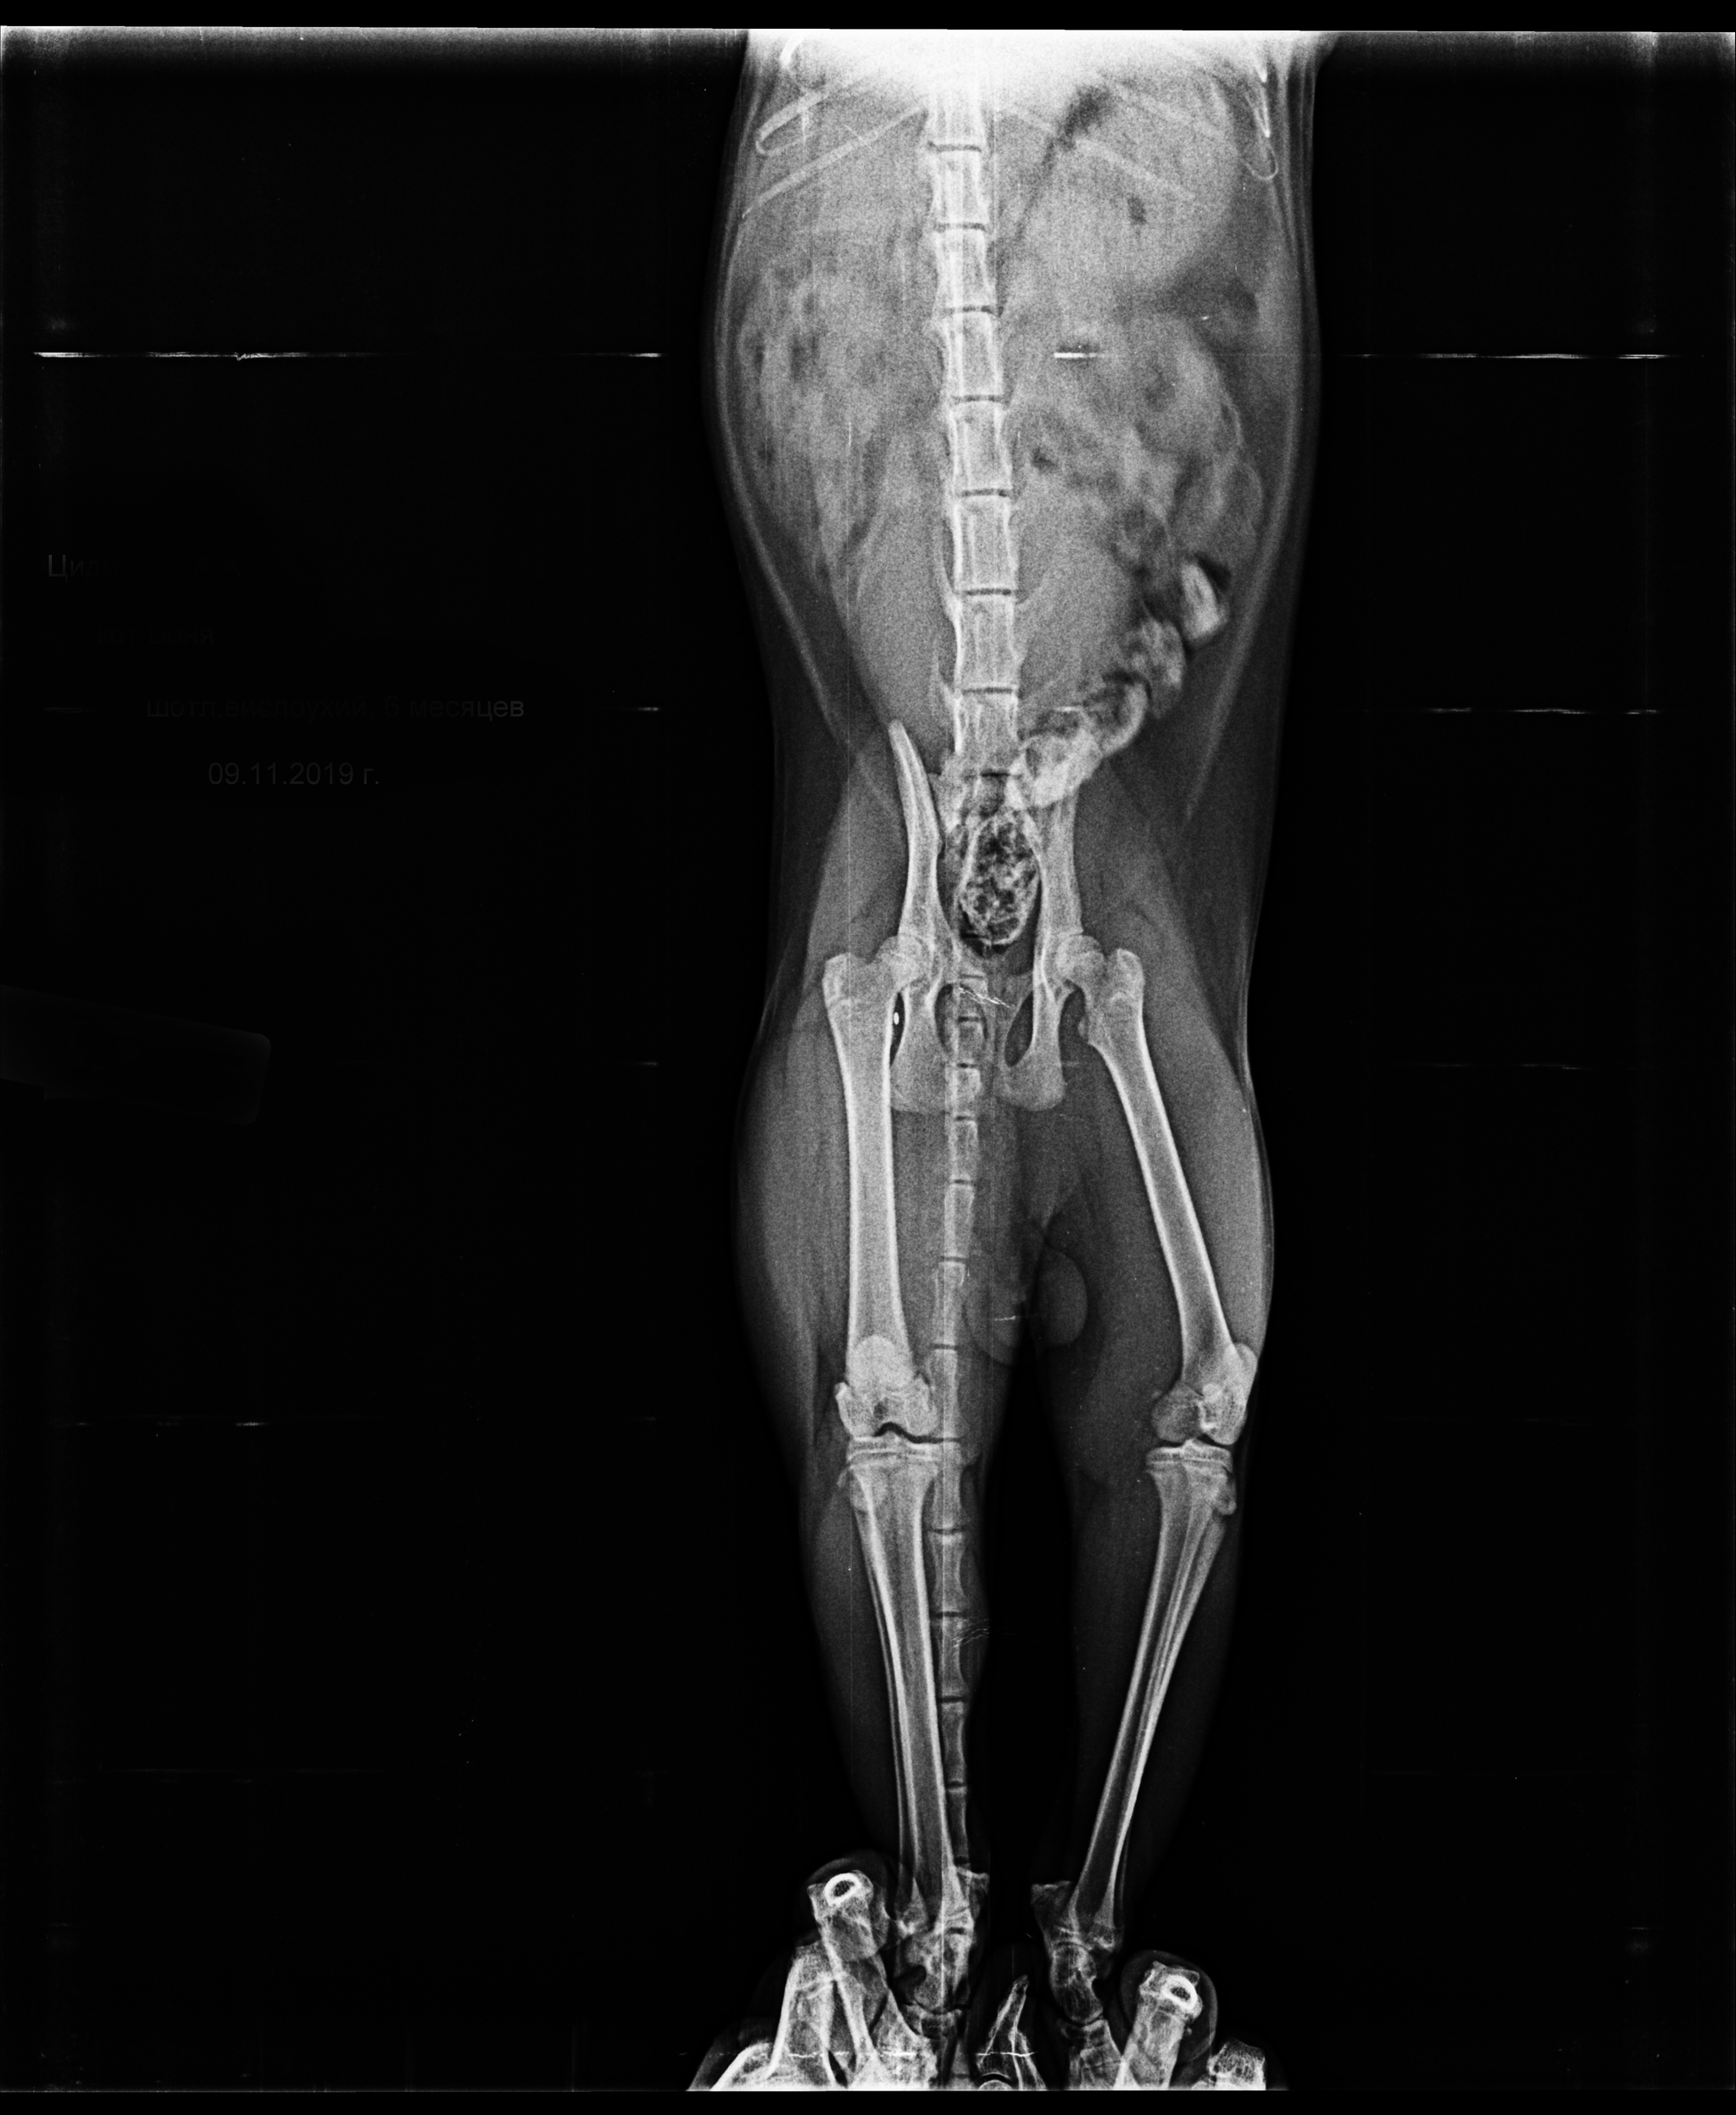

Вот как-то так выглядит кот напросвет. Теплоты там особо не видно, зато есть целый комплект косточек и перелом четвертой пястной кости.

Пока люди отвернулись, Линукс порвал сетку, вышел погулять на карниз и превратился в ракету класса "окно-асфальт". Жив, цел, орёл, месяц ходил со спицей в лапе, и всё равно умудрялся буянить по ночам.